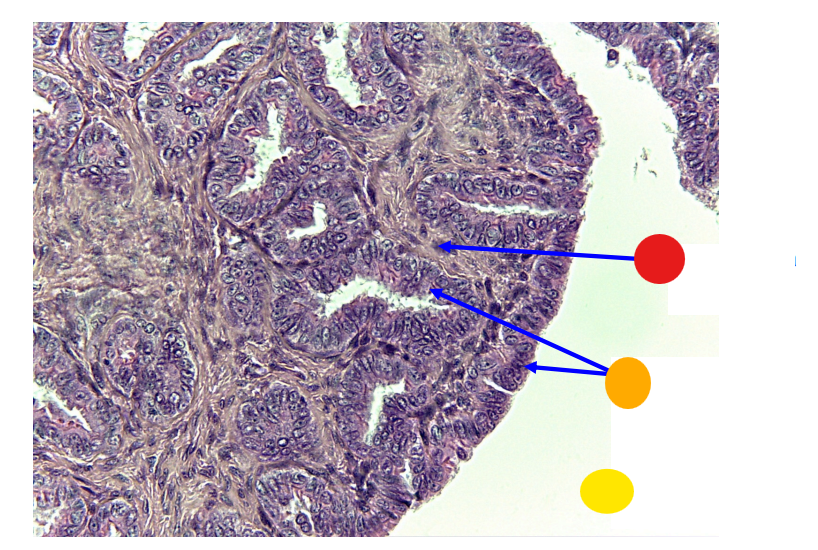

red

primordial follicles

red

primary follicles

red

tunica albuginea

orange

primary oocyte

yellow

primordial follicles

red

granulosa cells

orange

primary oocyte

what is this

primary follicle